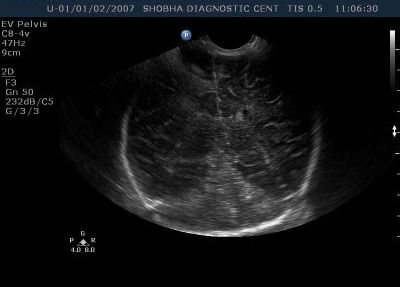

High Resolution Small Part Sonography / Musculoskeletal Sonography

All the superficial parts of the body like neck, thyroid, orbits, breast, any soft tissue swelling are best assessed on ultrasound.